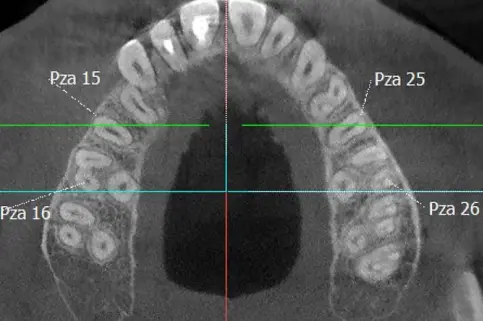

FOV 8x8 CM

Abarca la totalidad de la dentición, incluyendo el maxilar y la mandíbula, además de una porción de los senos maxilares.